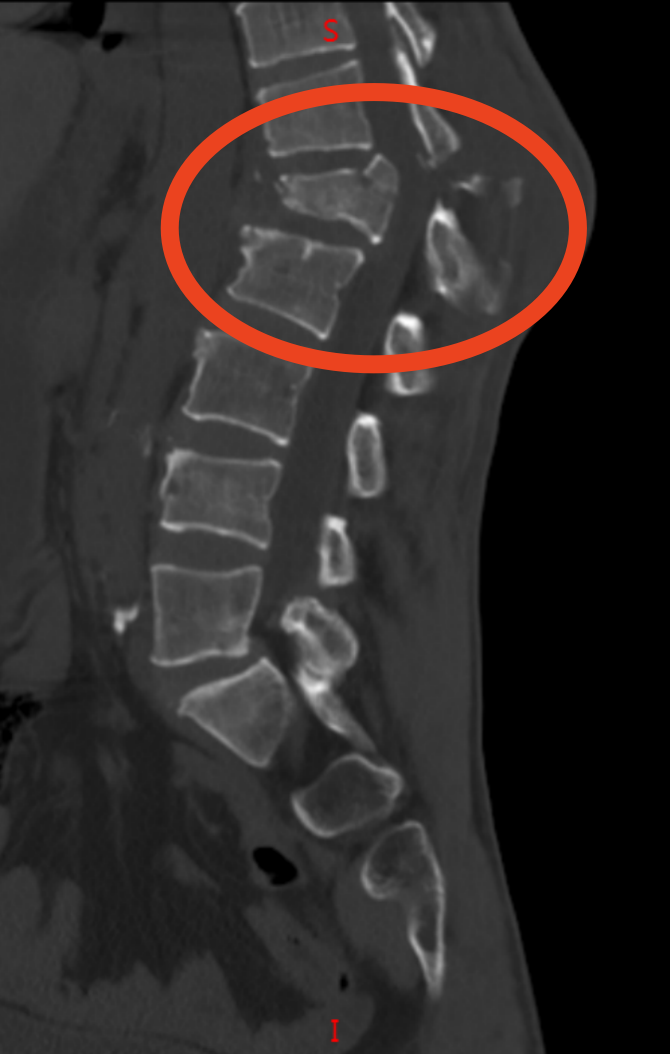

51 岁的李先生(化姓)因重物砸伤致腰部剧痛,被送到医院时,他双下肢麻木无力。检查显示,李先生的伤情极为复杂:L1 椎体呈屈曲 - 牵张型骨折,骨折块移位凸入椎管并出现硬膜外血肿,压迫脊髓,同时合并 T12、L2、L3、L4 多节段椎体骨折,L2-L4 双侧横突骨折,还伴有多发肋骨骨折及血气胸。医生指出,脊髓长期受压可能导致下肢瘫痪等不可逆后遗症,需立即手术干预。

脊柱外科满孝旭副主任医师带领手术团队针对李先生多节段脊柱骨折的特点,制定了精准的手术方案。术中,医生在全麻下为他实施 T12-L5 骨折切开复位内固定术,通过精准植入内固定器械,逐一矫正移位的椎体,重建脊柱正常序列与稳定性;同时仔细清除椎管内血肿,解除脊髓压迫,全程兼顾创伤控制与神经保护。

术后复查 CT 显示,李先生脊柱序列恢复良好,内固定位置精准,稳定性得到有效重建。